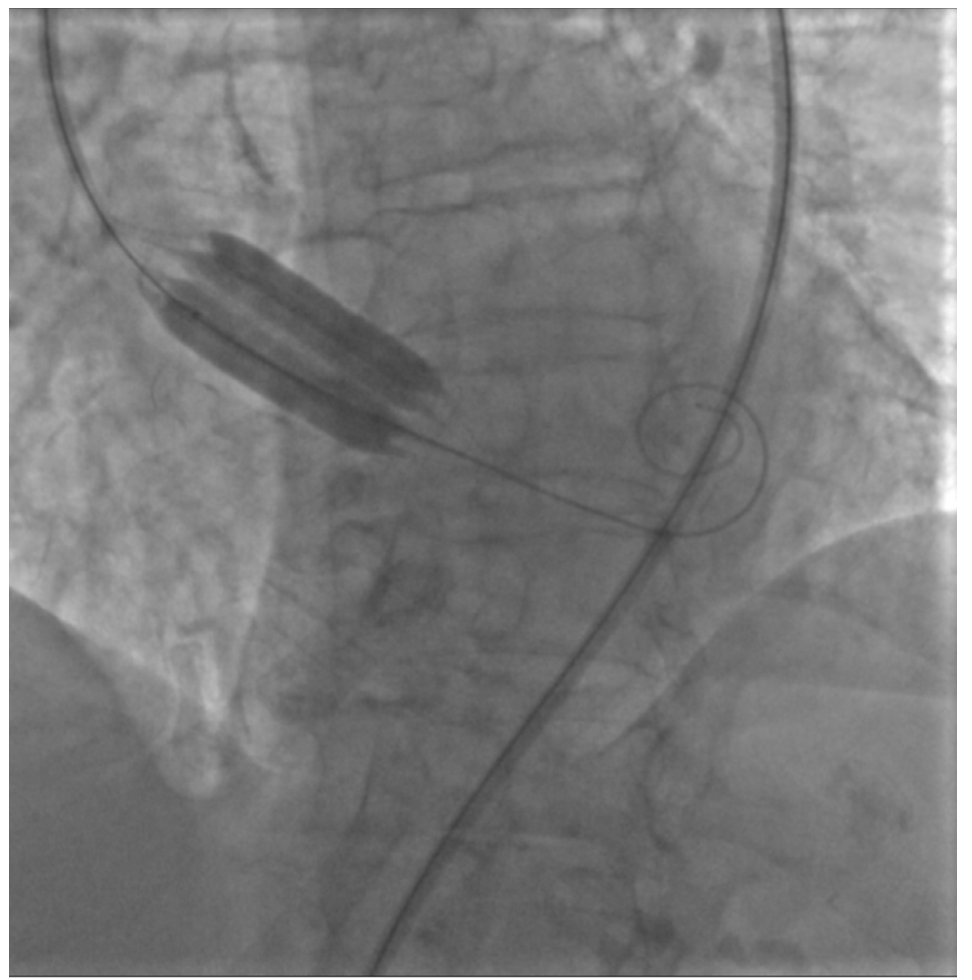

From 2018 to 2020, a total of 30 high-risk elderly patients, with a clinical manifestation of heart failure due to severe AS, were treated with BAV and were all prospectively included in the study. The Society of Thoracic Surgeons (STS) risk score was adopted to assess the cardiac mortality risk.9 Transaortic gradient was assessed by echocardiogram before BAV. All procedures were performed by femoral approach (right) employing a 12 Fr introducer sheath. Two vascular closure devices were predeployed prior to arterial sheath insertion and procedure initiation to allow suitable closure at the end of the case. Heparin 5000 IU was employed. We used True Flow perfusion-balloon valvuloplasty for aortic valve stenosis without RVP. Sixteen patients (53%) were treated with a 20- x 3.5-mm balloon and 14 patients (47%) with a 22- x 3.5-mm balloon. The diameter of balloons was based on transthoracic echocardiography. According to the guidelines of the American Society of Echocardiography, the aortic annulus was measured as the distance between the insertion of 2 adjacent leaflets on the parasternal long-axis view.10 Two balloon inflations (30 seconds each) were performed (Figure 1). All procedures were completed without RVP. Hemodynamic parameters were invasively evaluated during catheterization, before and immediately after BAV, at the same session. All device-related safety events were evaluated (device-related death, stroke, annulus rupture, coronary occlusion, or ventricular perforation during the dilation procedure). Vascular complications related to device insertion in the femoral-iliac axis were also investigated. All patients were regularly followed in order to detect the rate of mortality.